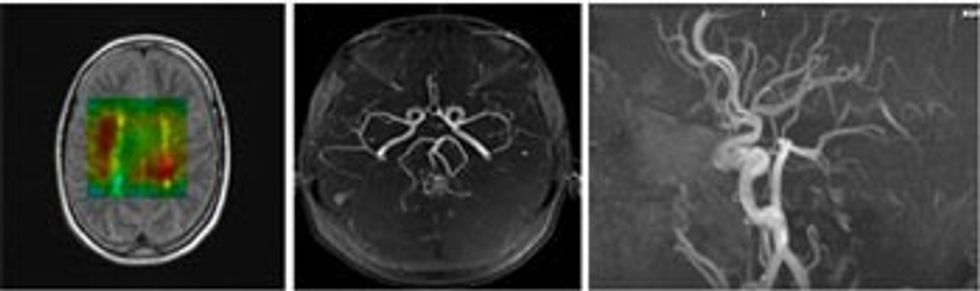

• IRM mundëson edhe punimin e angjiografisë (vizualizimi i enëve të gjakut përbrenda trupit) me RM (ARM), mundëson vizualizimin e enëve të gjakut të trurit pa përdorim të mjetit të kontrastit. Edhe në rast të përdorimit të mjetit të kontrastit për ARM rreziku për reaksione alergjike është jashtëzakonisht i ulët dhe dëmtimi i veshkave nuk haset.

• Sistemet e reja të IRM mundësojnë vizualizimin e funksionit të trurit, dhe mund të detektojnë inzultet iskemike (infarktin – ndërprerjen e qarkullimit të gjakut në tru) në fazat e hershme, më herët se çdo teknikë tjetër imazhuese.